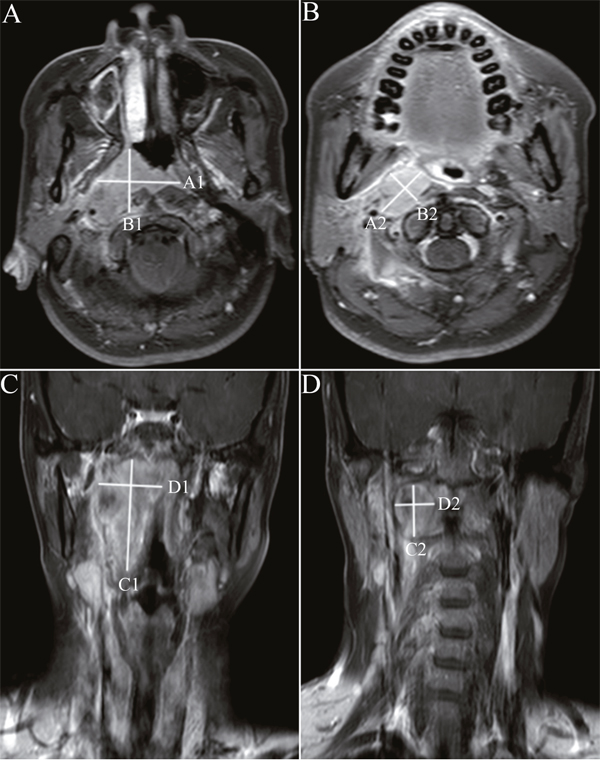

Imaging assessment

Measurements of primary tumor and retropharyngeal nodes were independently preformed by two radiologists who specialized in NPC with more than 10 years’ diagnostic experience of MRI. All measurements were conducted with the picture archiving and communication system (PACS). Retropharyngeal nodes with minimal axial diameter of ≥ 5 mm at diagnosis were regarded as malignant lesions which required to be measured. UDM was defined as the measurement of the maximum diameter of primary tumor and retropharyngeal nodes in either axial or coronal planes (Ax-UDM or Cor-UDM); BDM was defined as the product of the UDM and the greatest measurement perpendicular to the UDM in either axial or coronal planes (Ax-BDM or Cor-BDM) (Figure 1). In the event of skull base involvement without identifiable soft tissue components on pretreatment MRI scans, the bony skull base invasion was regarded as non-measurable lesions, as described in the RECIST 1.1 guidelines. In this case, the portion of bony structures was excluded from our measurement range on both pretreatment and post-treatment scans for the purpose of evaluation of tumor response.

Figure 1: Unidimensional and bidimensional measurements of nasopharyngeal carcinoma in axial and coronal T1-weighted postcontrast MR images. Notes: Ax-UDM was obtained by summation of maximum diameter of the primary tumor A. and retropharyngeal nodes B. in the largest axial slice. Ax-BDM was obtained by summation of the products of the Ax-UDM and the greatest measurement perpendicular to it (A) and retropharyngeal nodes (B). Cor-UDM and Cor-BDM of primary tumor C. and retropharyngeal nodes D. were obtained by the same measurements in the largest coronal slice. Ax-UDM (cm) =A1+A2; Ax-BDM (cm2) =A1×B1+A2×B2; Cor-UDM (cm) =C1+C2; Cor-BDM (cm2) =C1×D1+C2×D2

Abbreviations: Ax-UDM: unidimensional measurements in axial planes; Ax-BDM: bidimensional measurements in axial planes; Cor- UDM: unidimensional measurements in coronal planes; Cor-BDM: bidimensional measurements in coronal planes.